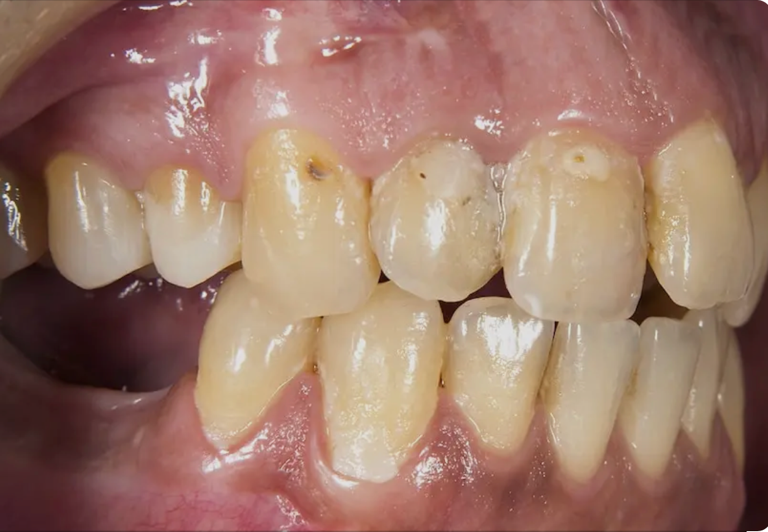

4. La pérdida de piezas altera todo el sistema

Cuando se pierde un diente y no se reemplaza, los dientes vecinos se desplazan, se altera la mordida y pueden aparecer nuevos problemas funcionales.